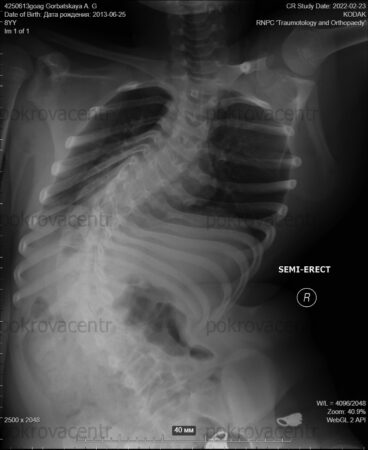

У одиннадцатилетней Анны Горбацкой (25.06.2013 г. р.) нейромышечный сколиоз на фоне ВПР спинного мозга.

На фото рентген за 2022 год, сейчас еще хуже, говорят родители.